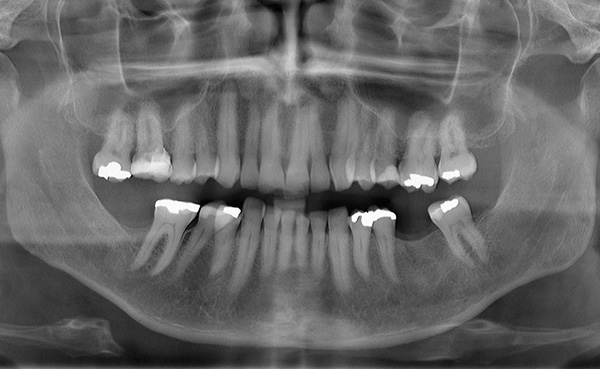

A foto abaixo mostra os implantes removidos da mandíbula:

Nas pequenas situações em que, por alguns motivos, dependendo ou não do médico, os implantes instalados na mandíbula são rejeitados, ocorre uma diminuição banal no tecido ósseo. Essa diminuição óssea no futuro pode ser facilmente compensada por sua restauração artificial usando um enxerto ósseo.